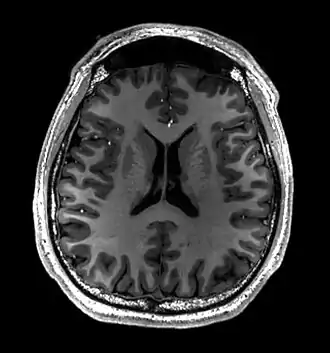

Brain regions on T1 MRI

- T1-weighted (T1W) images: Cerebrospinal fluid is dark. T1-weighted images are useful for visualizing normal anatomy.